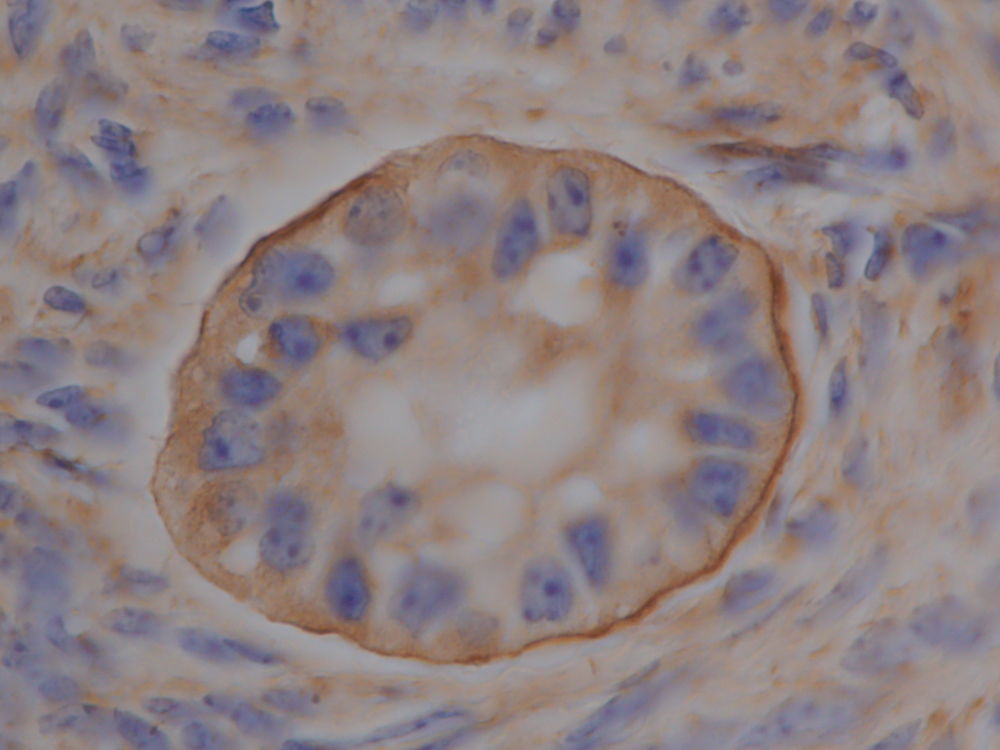

La criopreservación de ovocitos sigue considerándose una técnica que se encuentra en fase experimental, debido a la ensibilidad del ovocito a las bajas temperaturas. Un desafío adicional para la preservación de la fertilidad femenina es que, a pesar de la gran cantidad de células germinales presentes en el ovario, el número de ovocitos susceptibles de ser criopreservados, o de ser incorporados a un protocolo de producción de embriones in vitro (IVP) es muy reducido, lo que da lugar a un desperdicio no deseable de Recursos Genéticos (RG). En este contexto, el objetivo gral de MOTHER es investigar las condiciones óptimas de criopreservación de la corteza ovárica bovina para salvaguardar las diferentes poblaciones de folículos presentes en el ovario. Además, abordará el desarrollo de un innovador sistema de cultivo in vitro (CIV) que permitirá recuperar los ovocitos procedentes de folículos ováricos en tejido crioconservado y llevarlos a una fase de desarrollo compatible con su utilización en IVP.